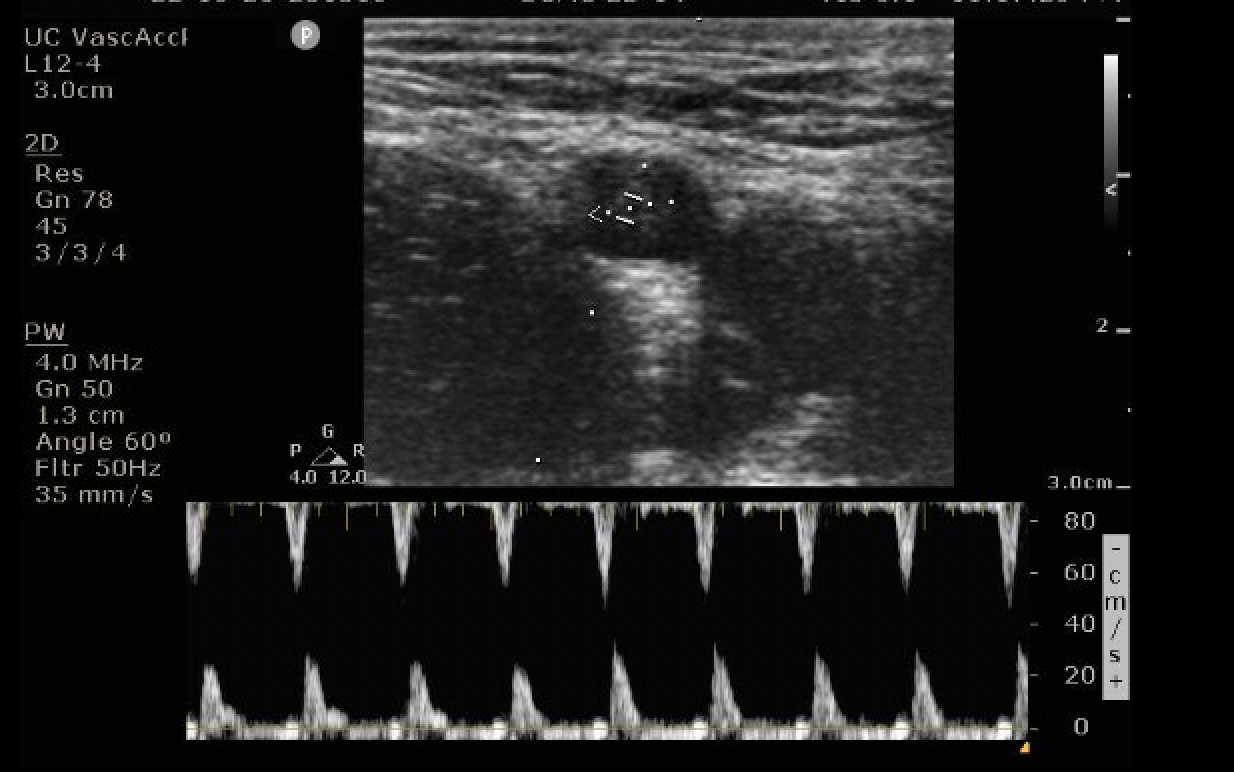

How to utilize power doppler to find the femoral pulse using ultrasound

Chose a linear probe, in vascular setting

Find your anatomy

Select power doppler and place the marker in the artery

Click power doppler again for the flow

Utilize your baseline and scale to make adjustments so you can see the entirety of the forward flow velocities

Image 1. Right femoral region with the femoral artery and vein displayed

Image 2. Choose power doppler (PW) seen in the yellow box and select it again once the marker is in the middle of the vessel. Use the baseline and scale buttons to optimize your image

Image 3. Cursor through the femoral artery. Peak systolic velocity (PSV) scale on the right. Max PSV > 20 cm/s